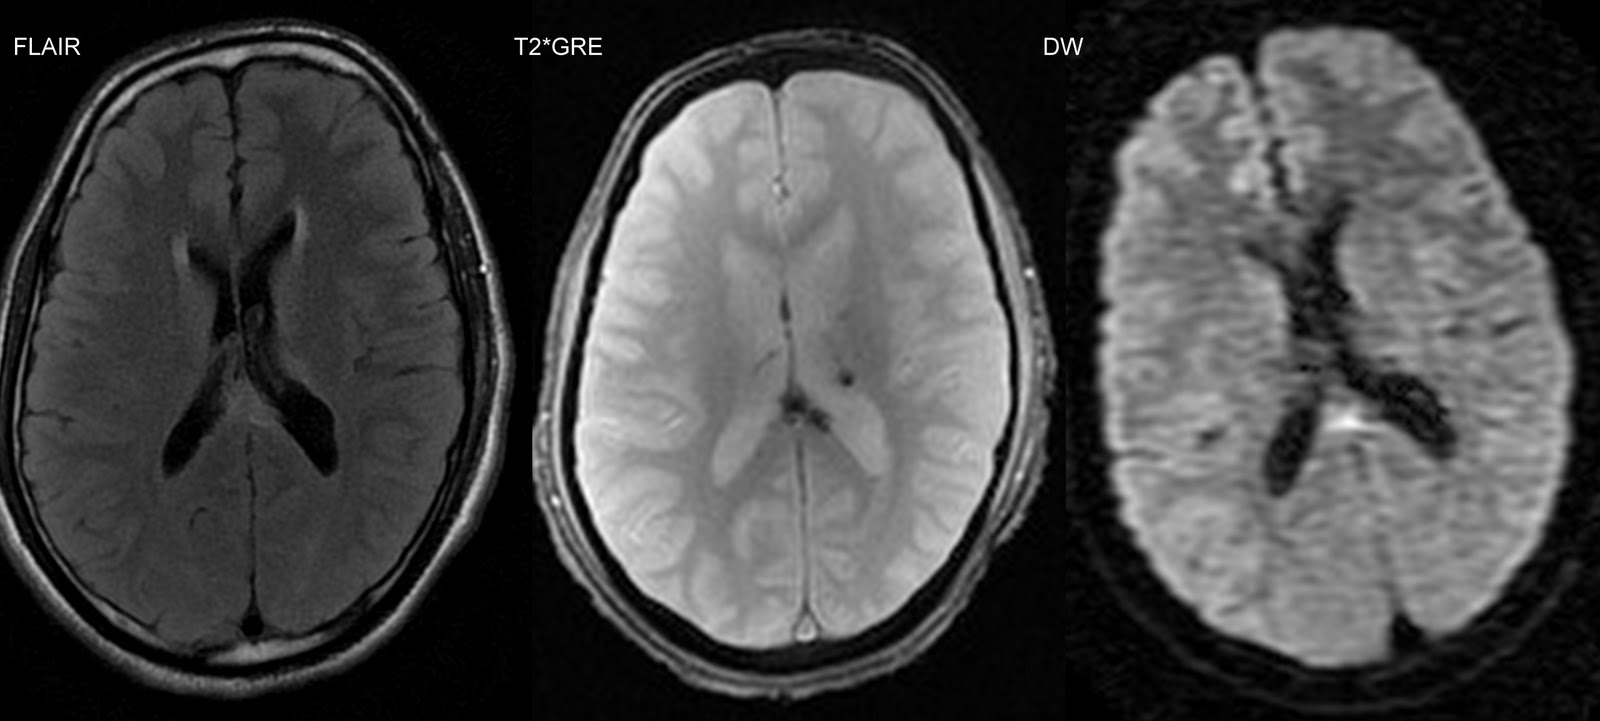

Images In Neuroscience: Question Restricted diffusion On MR ...

Restricted diffusion on MR imaging of an acute cerebral lesion Jeyaraj D. Pandiana, Thulasi Rajah b, Alan Coulthard , Michael P. Pendera, c An MRI brain scan was performed 3 days after the onset of symptoms (Fig. 1 and Fig. 2). Fig. 1. ... Read More

Restricted Diffusion On Magnetic Resonance Imaging In Partial ...

B D A C Figure 1. Diffusion-weighted magnetic resonance images during partial status epilepticus show restricted diffusion in a gyriform pattern in the right ... View Doc